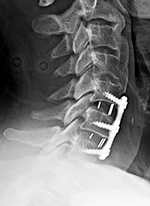

| An anterior cervical fixation plate and screws has been placed with PEEK disk cages at C5-6 and C6-7. |

Three months after surgery the disk cage at C6-7 has subsided and slipped anteriorly. |